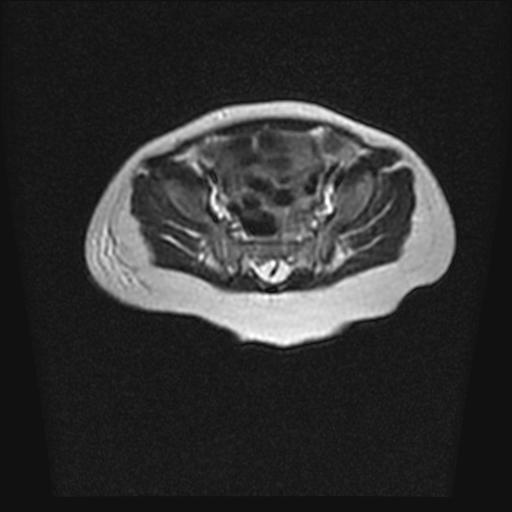

标题: PED0016:脊膜膨出 [打印本页]

标题: PED0016:脊膜膨出

四个月的女婴,ct示脊膜膨出.

脊柱裂、脊膜膨出,请结合临床除外皮毛窦。

脂肪脊髓脊膜膨出

脊柱裂、脊膜膨出